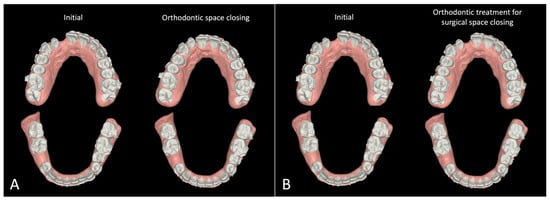

3.1. Step 1: Virtual Orthodontic Setup

| Option 1. Orthodontic Space Closure | Option 2. Surgical Space Closure | ||

|---|---|---|---|

| Orthognathic surgery (surgery first) | Orthognathic surgery (surgery first) | ||

| Maxilla | LeFort I osteotomy to advance the maxilla | Maxilla | LeFort I osteotomy to advance the maxilla |

| 2-piece segmental osteotomy to close the gap | |||

| Mandible | Sagittal split ramus osteotomy to setback the mandible and correct the facial asymmetry | Mandible | Sagittal split ramus osteotomy to setback the mandible and correct the facial asymmetry |

| Post-surgical orthodontics | Post-surgical orthodontics | ||

| Space closure | Decompensation | ||

| Decompensation | Finishing and Detailing | ||

| Finishing and Detailing | |||